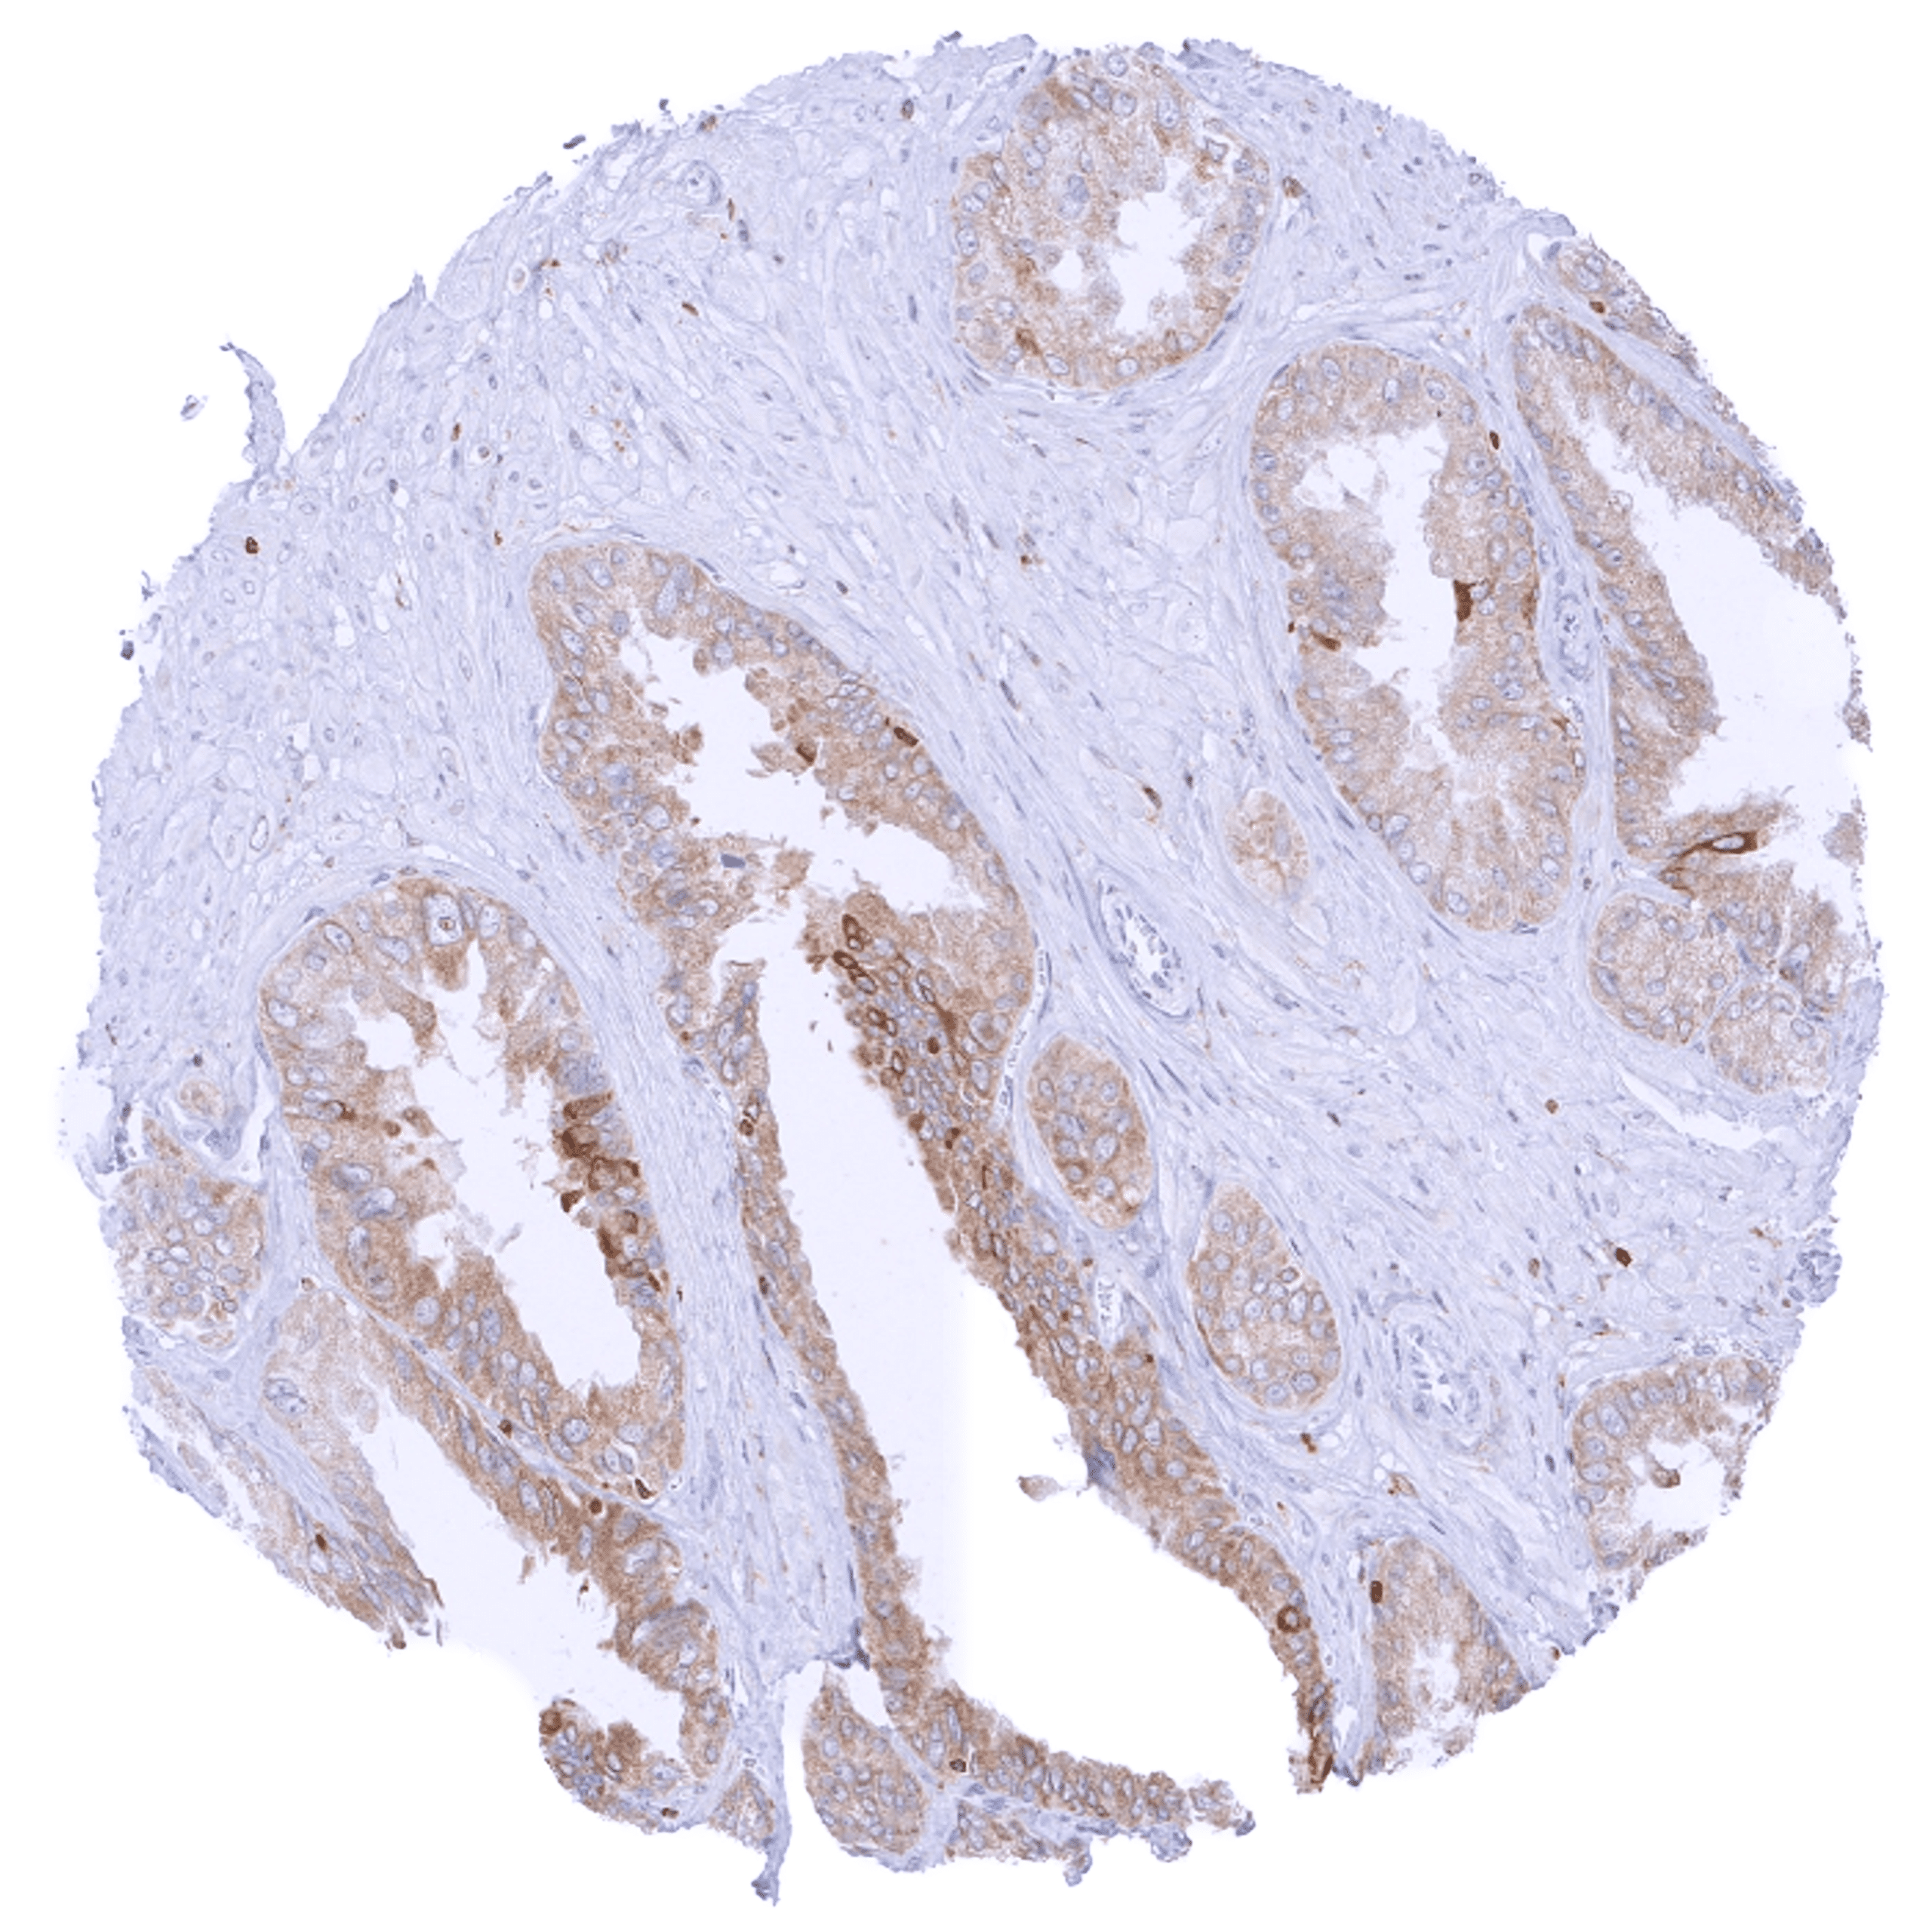

| Female genital | Breast | Distinct cytoplasmic bcl-2 staining of epithelial cells (acinar cells stain stronger than myoepithelial cells). |